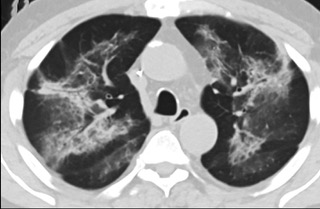

6天后的軸向CT平掃圖像顯示毛玻璃影變為實變和輕度結構扭曲。(同一病人CT影像)

16位被文獻報道為電子煙肺炎的患者被專家判定為“病毒性感染”,即有可能是新冠肺炎的“疑診患者”,其中更有5位臨床癥狀和治療情況相對完整的患者被判定為“中度可疑”。因此在2019年美國報道的電子煙肺炎中存在病毒性感染的病例,而且不排除美國電子煙肺炎中存在新冠肺炎的可能性。